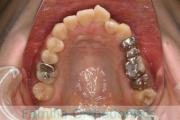

- ≫治療中 ステップ1

上顎

下顎

前歯の関係など

右側

正面

左側